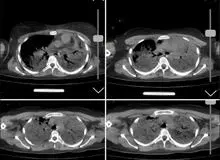

ارگان رسانه ای نزدیک به سپاه انتشار تصاویر مربوط به سی تی اسکن مهسا امینی را تایید کرد.